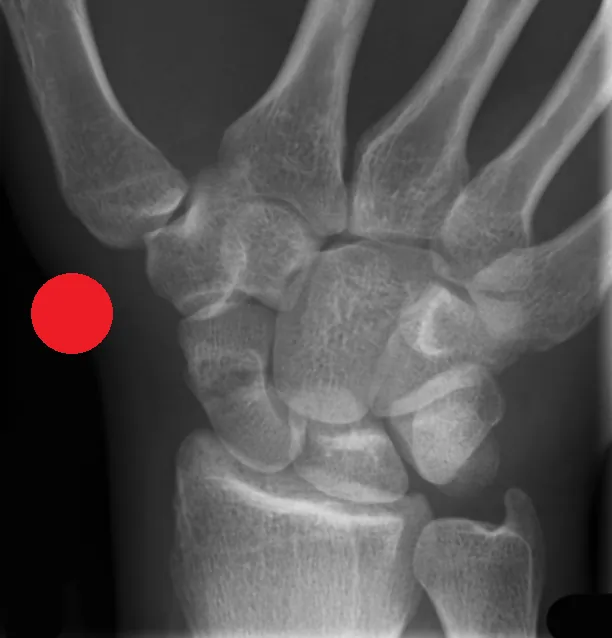

This Red Dot X-Ray Interpretation Course is designed for Current Advanced Practice Practitioners including Advanced Nurse Practitioners and Advanced Physiotherapist Practitioners working in acute MSK care, for example in A/E or minor injuries and who are seeking to enhance confidence and improve their diagnostic assessment and accuracy. The course focuses on the identification and escalation of suspected pathology, fractures, or other deviations from normal imaging appearances. Participants will build robust knowledge and improve their ability to flag potentially critical findings.

The course focuses on improving the skills needed to identify a range of acute pathologies on x-rays, including fractures, dislocations, chest abnormalities and more. The course will improve patient safety by reducing missed urgent findings, especially whilst waiting for report completion.

• Improved identification of key radiographic features of common acute pathologies, eg. fractures, dislocations, pneumothorax.

• Improved ability to distinguish between normal anatomical variants and common pathological findings on Radiographs.